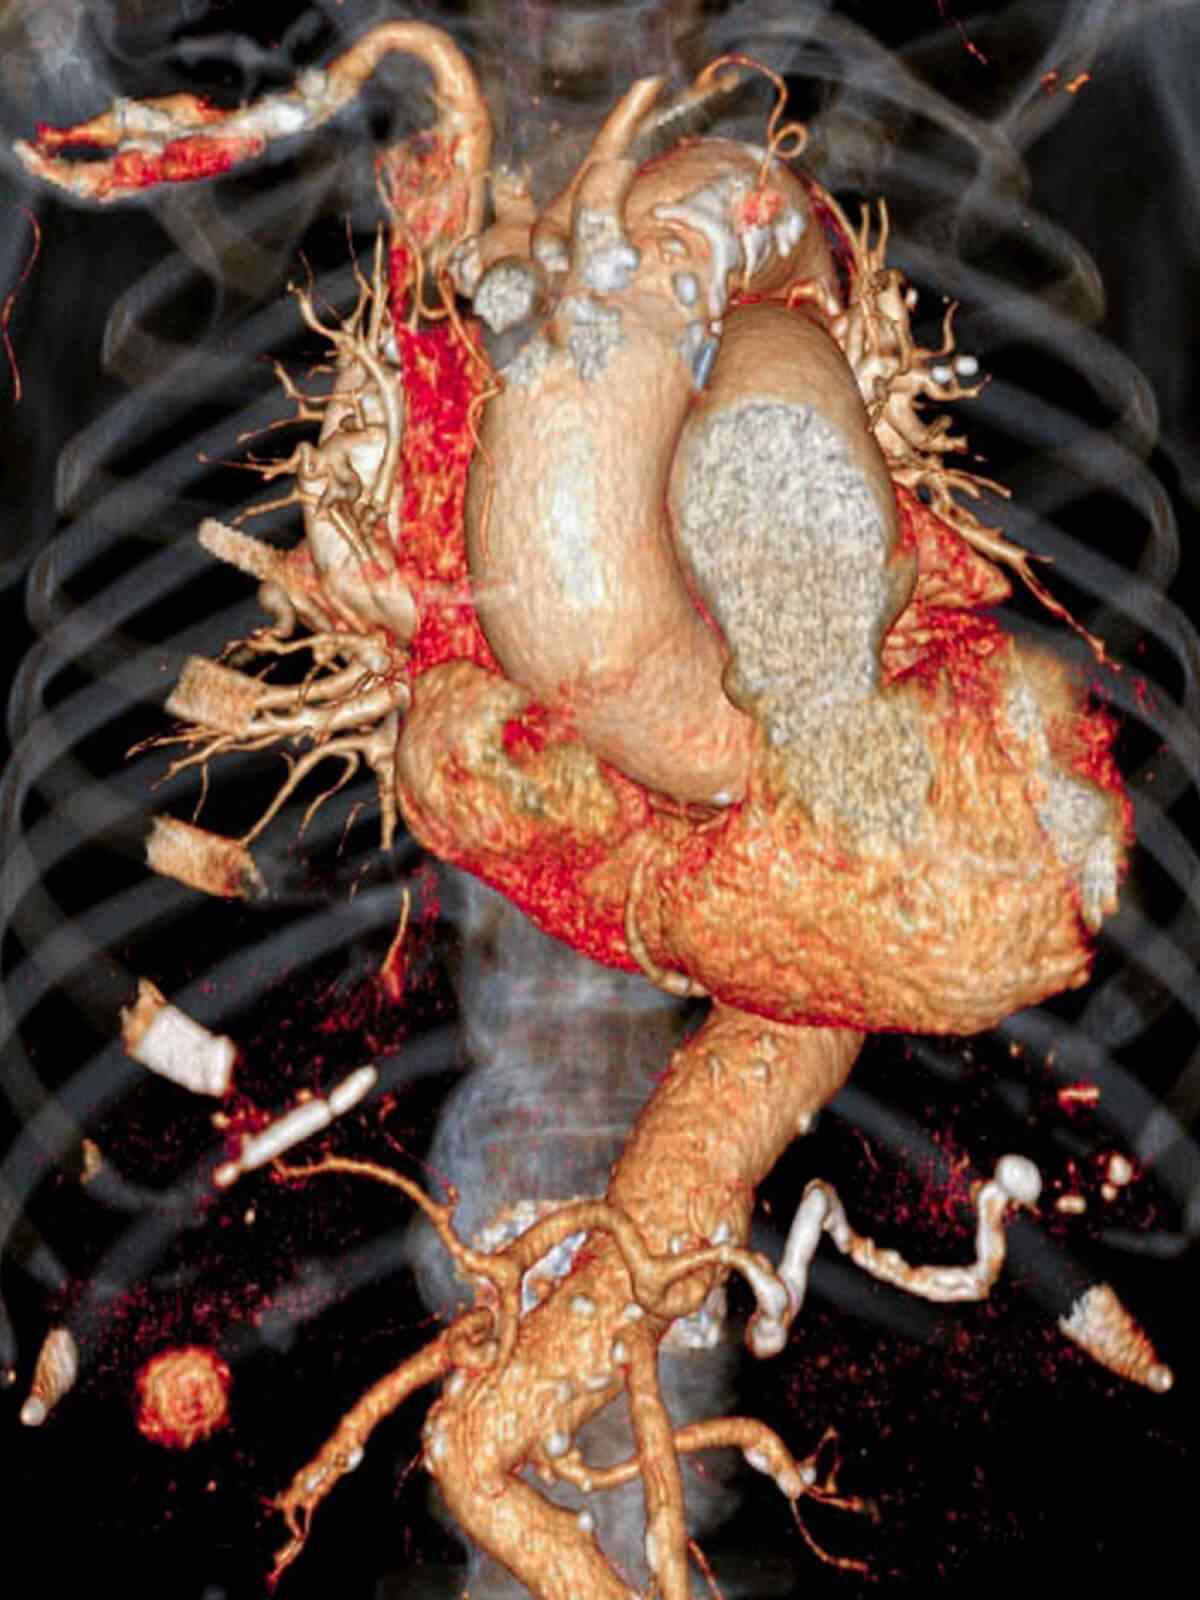

If you have known coronary artery disease, your doctor might recommend the traditional approach because you can also receive treatment during the procedure. Your doctor should give you instructions about how to prepare for CT.

Angioplasty uses a tiny balloon catheter that is inserted in a blocked blood vessel to help widen it and improve blood flow to your heart. Angioplasty is often combined with the placement of a small wire mesh tube called a stent. The stent helps prop the artery open, decreasing its chance of narrowing again.